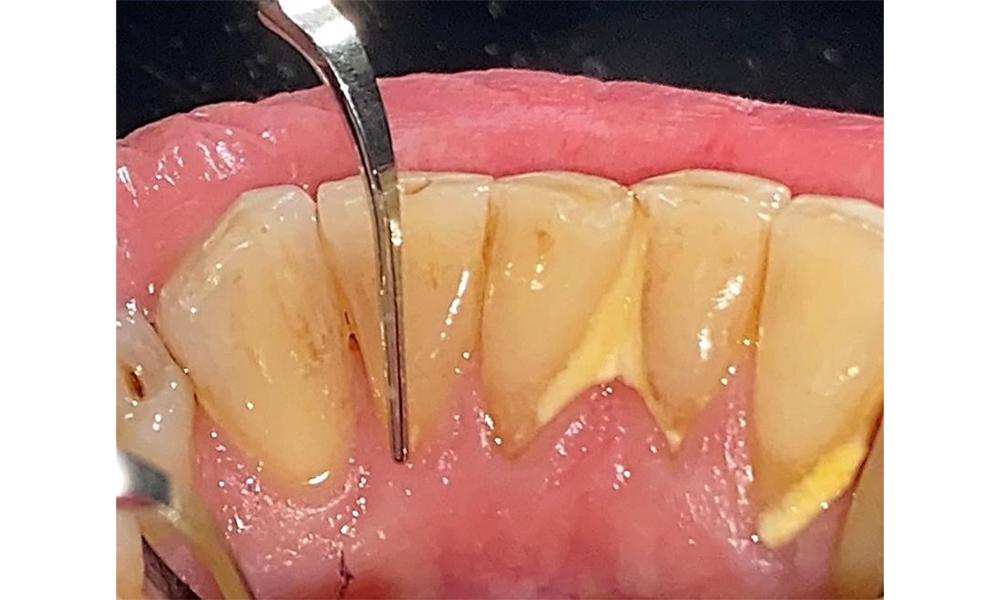

The patient has a full dentition with 28 teeth, which includes amalgam and composite fillings in the molar and premolar regions. There is a visible clinical marginal gap present on tooth 14. Tooth 27 has an adequate gold inlay. There are also generalized attritions and abrasions. (Fig. 2, Fig. 3, Fig. 4, Fig. 5, Fig. 6)

The patient has stage II, grade B periodontitis (5). At 1 to 3 mm, the clinical probing depths were within the physiological range. Localized probing depths of 5 mm were observed on the mesiopalatal aspects on both 17 and 27. There are generalized recessions of 1–3 mm with partial loss of the interdental papillae (Fig. 2, Fig. 3, Fig. 4)